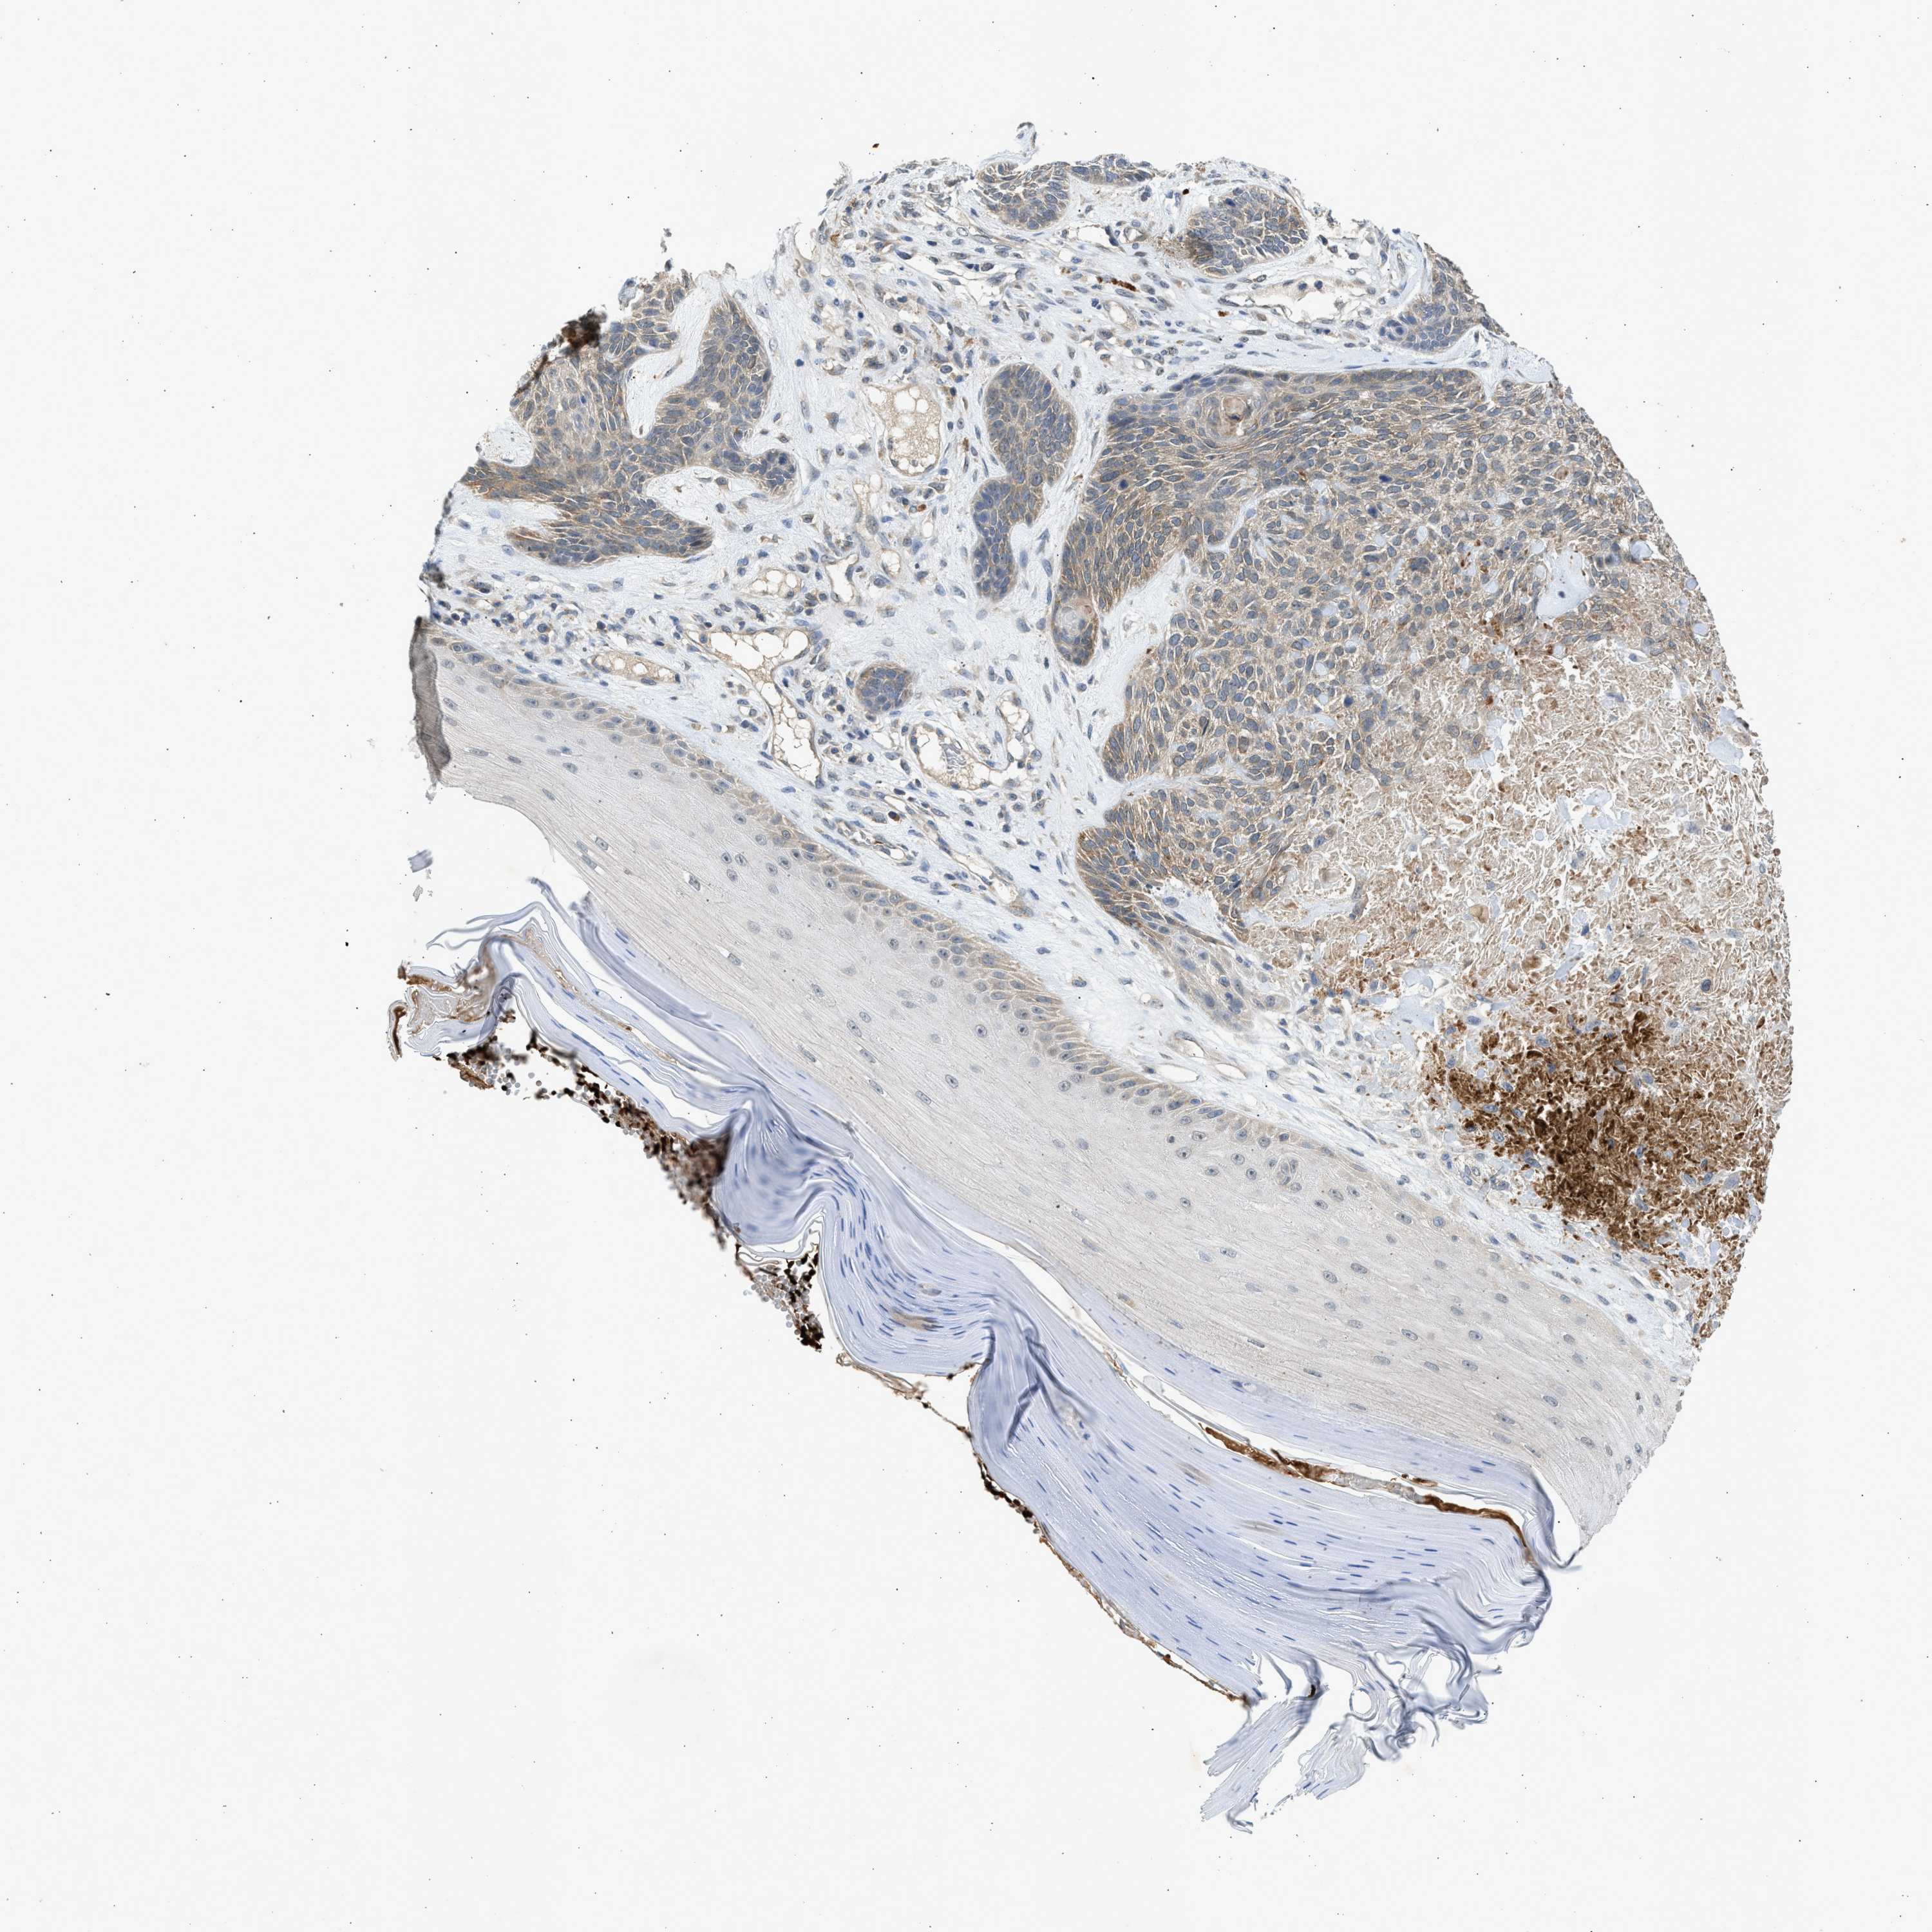

SKIN CANCER - Protein expressioni

A mouse-over function shows sample information and annotation data. Click on an image to view it in a full screen mode. Samples can be filtered based on level of antibody staining by selecting one or several of the following categories: high, medium, low and not detected. The assay and annotation is described here.

Each image is clickable and will lead to virtual microscopy that enables deeper exploration of all samples and also displays staining intensity scores, fraction scores and subcellular localization as well as patient and tissue information for each sample.

Antibody CAB018561

Staining

High

Intensity

Strong

Quantity

>75%

Location

Nuclear

Squamous cell carcinoma in situ, NOS

Squamous cell carcinoma, NOS